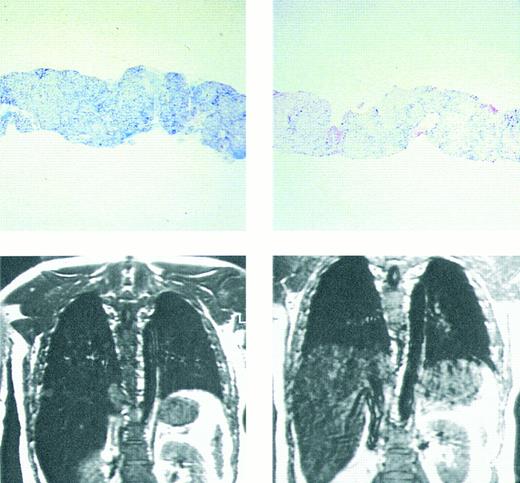

Imaging of tissue iron.Computed tomography,170-174 nuclear resonance scattering (NRS) from manganese-56,175 and the most widely used modality, magnetic resonance imaging,176-193 have all been used to evaluate tissue iron stores in vitro and in vivo, but none is clinically available for the measurement of hepatic iron concentrations. Biopsy-demonstrated reductions in hepatic iron have been reflected by magnetic resonance imaging (MRI) in individual patients192 (Fig 3), but correlations between hepatic iron concentrations determined by biopsy and those estimated by magnetic resonance have varied with differences in both equipment and method. Magnetic resonance represents the only imaging method in clinical use with the potential to detect iron within the heart189,192,193 (Fig 4). Although imprecision in the quantitation of cardiac iron obtained at biopsy194,195 prevents direct correlation with values of cardiac iron estimated by MRI in humans, good correlation between MRI-derived, and biopsy-determined, cardiac iron has been observed in a thalassemic mouse model.193 Furthermore, MRI changes consistent with the reduction of cardiac iron (Fig 5) that are paralleled by improvement in cardiac function have been reported in individual patients.192 Similarly, MRI studies of the iron-loaded anterior pituitary gland196,197 have reported variations in pituitary iron that are correlated with pituitary reserve in individual patients with thalassemia.198 In summary, although many studies show that MRI can reflect the presence of, and changes in, tissue iron in vivo, this method has not been validated as one that provides measurements of tissue iron that are quantitatively equivalent to those determined at tissue biopsy.

Prussian blue stain showing (top figures) hepatic iron in hepatocytes and portal macrophages, before (left) and after (right) 9 months of chelating therapy with the orally active chelating agent deferiprone in a patient with homozygous β thalassemia. Hepatic iron concentration in the sample on left was approximately 16 mg/g dry weight liver tissue; in that on the right hepatic iron concentration was less than 2 mg/g dry weight tissue. Coronal MRI (lower figures) of hepatic iron before (left) and after (right) therapy with the orally active iron chelating agent deferiprone in the same patient. Complete absence of liver signal in the MRI on the left is compatible with significant iron deposition, while improvement in signal intensity after 9 months of therapy (right) indicates that the liver iron content is reduced compared with that of the previous study. (Reprinted with permission.192 )